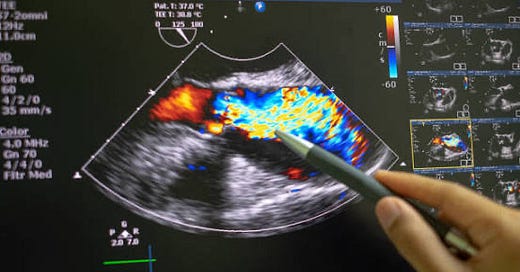

A New Kind of Ultrasound Sensor Could Transform Wearable Health Devices